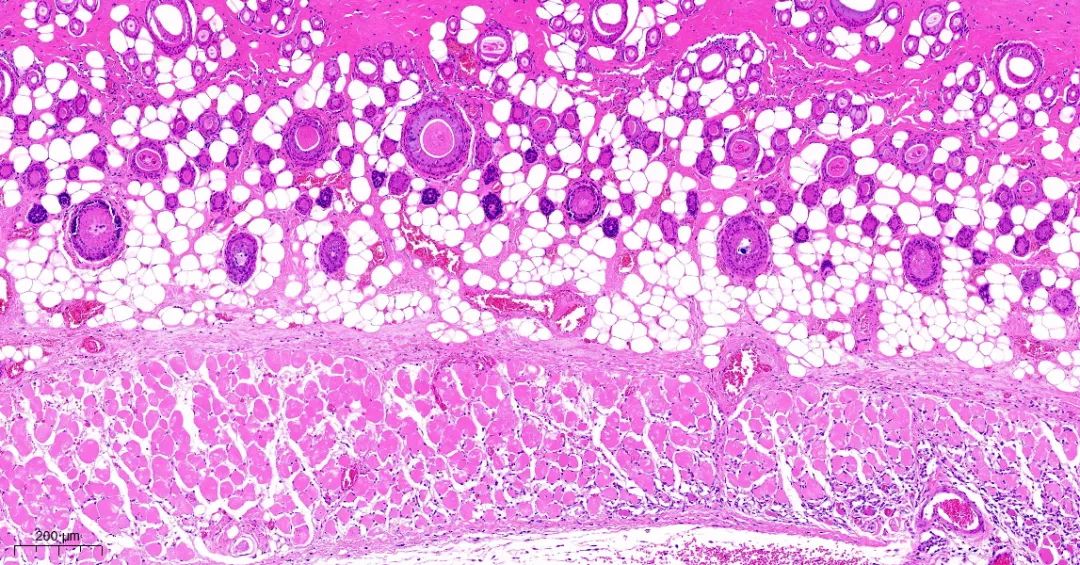

取正常对照组及模型组大鼠背部皮肤标本,常规固定,石蜡切片,HE染色,观察皮肤组织学变化。

模型2组皮组织切片对比